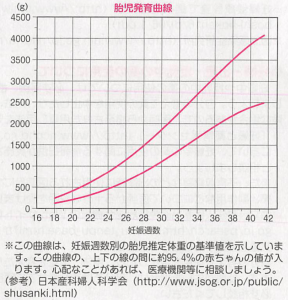

母子手帳「胎児発育曲線 新生児の成長曲線 」の見方と活用法-おむつのムーニー 公式 ユニ・チャーム。

医師監修 胎児の発育曲線 成長曲線 とは?どのように見ればいいの?ゼクシィBaby。

胎児発育曲線ギリギリ成長の小ささで16週から34週まで育ってるべびお君。 - 保育士うたのサイト。

胎児発育曲線』とは?週ごとの発育の目安を助産師が解説◎ - 株式会社エバーセンス。

胎児発育曲線』とは?週ごとの発育の目安を助産師が解説◎ - 株式会社エバーセンス。

胎児発育曲線の±2.0SDの意味は?エコー写真に学ぶ統計学 - 日常を少し掘り下げてみる。

医師監修 おなかの赤ちゃんの発育は順調? 「胎児発育曲線」とはトモニテ。

胎児発育曲線の±2.0SDの意味は?エコー写真に学ぶ統計学 - 日常を少し掘り下げてみる。

母子手帳「胎児発育曲線 新生児の成長曲線 」の見方と活用法-おむつのムーニー 公式 ユニ・チャーム。